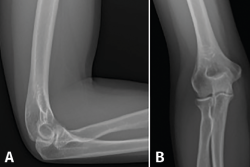

Cuando los síntomas clínicos no están bien definidos, es útil recurrir a técnicas diagnósticas como la radiografía simple anteroposterior y lateral del codo, que debe realizarse de rutina en pacientes con síntomas de larga evolución para descartar posibles diagnósticos alternativos(13).

Las radiografías simples constituyen un método diagnóstico barato y accesible (Figura 5); con ellas se puede realizar la valoración de patologías óseas, como la osteocondritis disecante, diversas artropatías y la existencia de cuerpos libres. En casos de tendinopatías de larga evolución, se pueden llegar a ver calcificaciones de la inserción del extensor carpi radialis brevis (ECRB)(14).

Figura 5. Radiografía anteroposterior y lateral del codo. Habitualmente, no muestran ninguna alteración, salvo en casos de larga evolución en los que se pueden ver calcificaciones del extensor carpi radialis brevis.